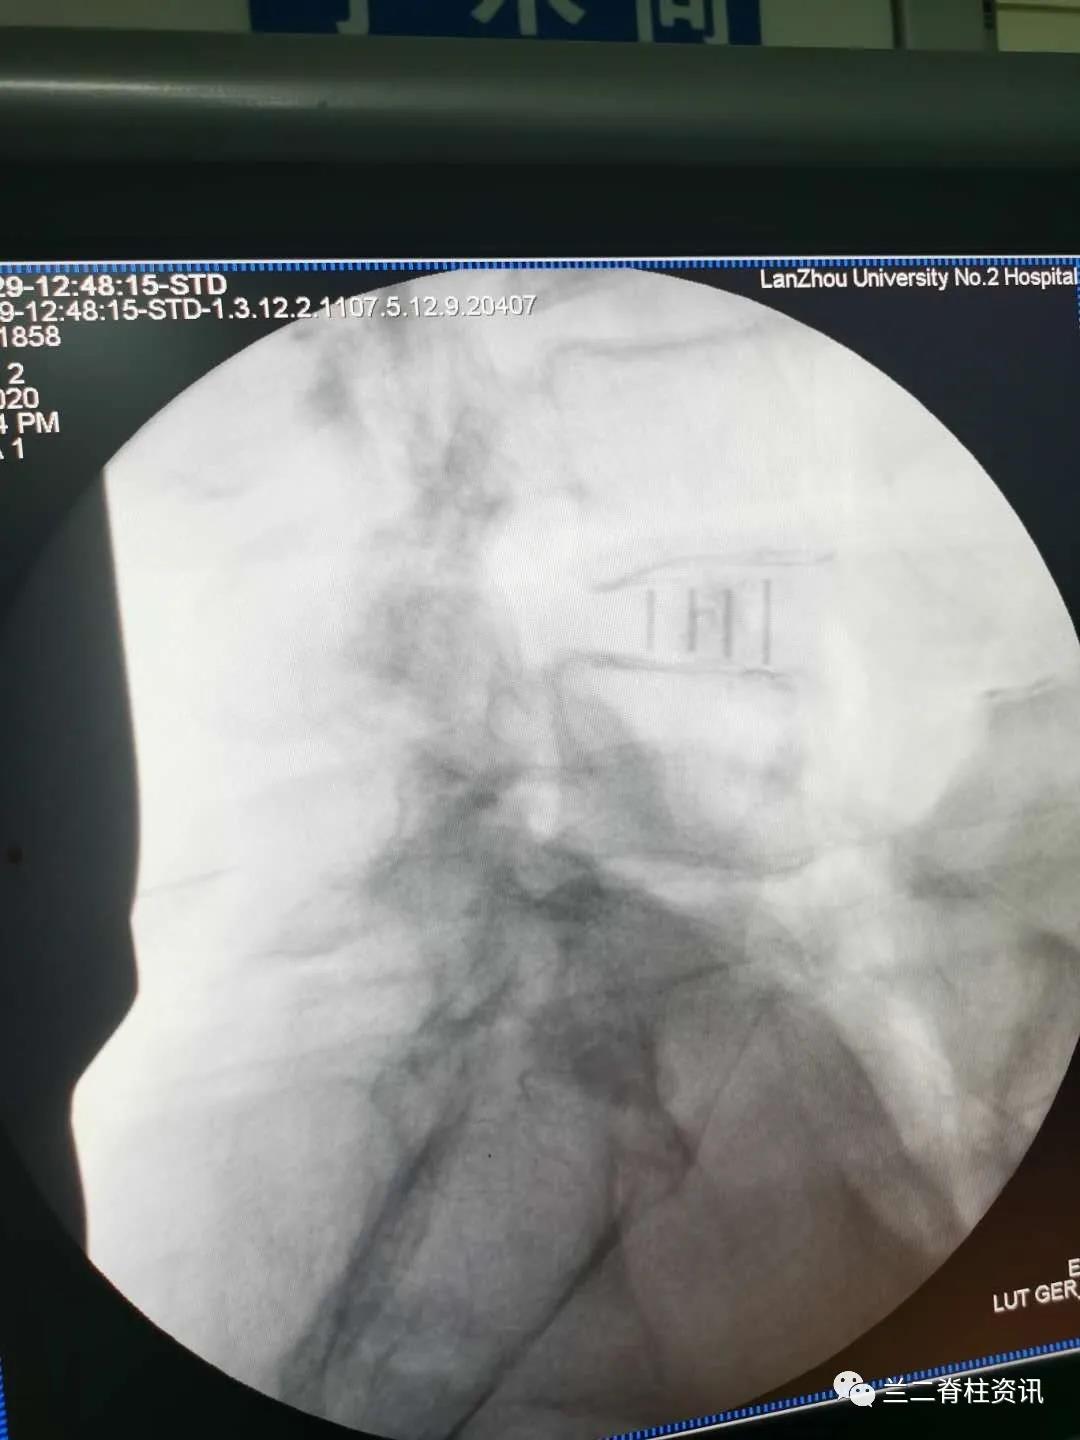

通常OLIF手术需用侧卧位微创植入融合器后变换体位(俯卧位)植入经皮椎弓根钉,该患者采用单一体位OLIF 融合术 ,利用c臂“徒手”植入经皮椎弓根螺钉。该技术允许在单一体位下“毕其功于一役”,简化了手术流程,缩短了手术时间,减少感染风险,降低变换体位导致的麻醉脱管等并发症,促进了术后康复,大大缩短了手术时间,真正实现了“高效、可视、精准、安全”的脊柱微创治疗理念。本例手术的成果,也标志着我院骨科在脊柱微创领域方面走在了国内前沿。